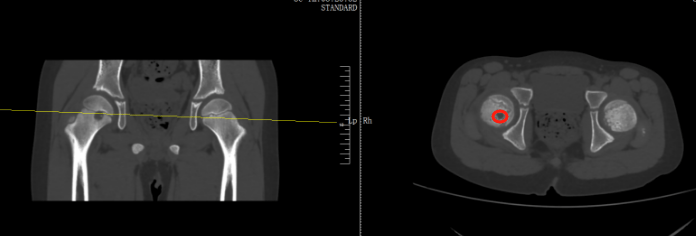

检查后,医生发现,肿瘤直径约有20厘米,基本占满了女孩的右侧屁股,万幸还未出现远处转移,可以通过手术将肿瘤剥离那可恩普拉托姆联vs查英特贺纳比尔 。

当地医生诊断为右股骨近端占位,怀疑内部可能长了肿瘤那可恩普拉托姆联vs查英特贺纳比尔 。扬扬妈妈听到医生的话心里直害怕,夫妻两人又马不停蹄带孩子来到了骨科医院进一步检查,扬扬被确诊为右股骨近端肿瘤。

好在从影像上来看,初步考虑是偏良性那可恩普拉托姆联vs查英特贺纳比尔 。在跟家长商讨过后,医生为扬扬执行了前侧入路右侧股骨头钻取刮除、取自体髂骨骨移植术,手术顺利切除病灶,并补上了股骨的“漏洞”。